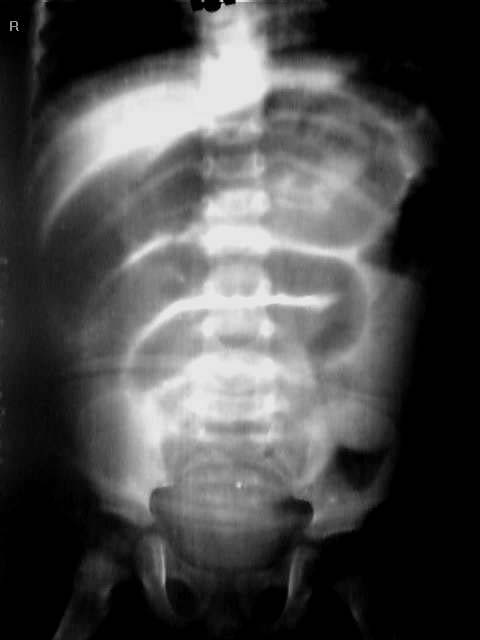

立位腹平片和仰卧位腹平片显示:腹部气液平和小肠管积气扩张,盆腔小肠影及结肠未见气体影.考虑炎性狭窄及粘连性肠梗阻.

术后诊断:肠套叠。术中所见:腹腔有少量淡血性液体,全小肠充气,轻度发绀。腹腔左侧探及蜡肠样肠管约12厘米,重度发绀。

肠套叠中一重要征象是套叠肿块征。由于受到套叠发生、发展及回盲部系膜的影响,套叠肿块可位于右上腹、腹中部、左腹、甚至下腹部。本例套叠肿块位于左腹(红箭头标示)。